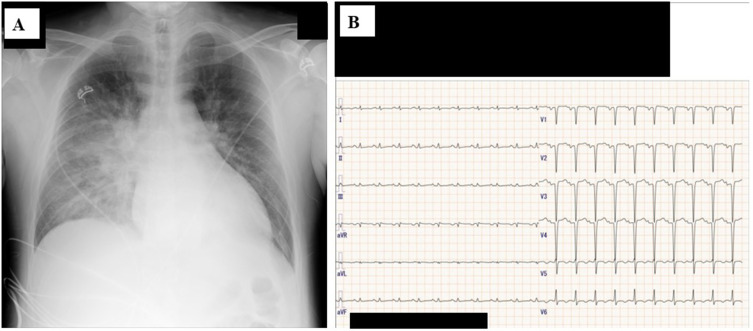

Three cases of severe influenza that required ventilator management in the 2024-2025 season, which was a major influenza season in Japan, are presented. Case 1: A 54-year-old man with obesity developed lobar pneumonia as a result of severe community-acquired pneumonia (CAP) secondary to methicillin-susceptible Staphylococcus aureus (MSSA), as confirmed on sputum culture. The nasal swab was positive for influenza A antigen. Intravenous peramivir and piperacillin/tazobactam were administered for 2 days followed by lascufloxacin and linezolid for 2 weeks. Veno-venous extracorporeal membrane oxygenation (VV-ECMO) was also performed. Case 2: A 63-year-old man with multiple myeloma and chronic kidney disease developed severe pneumonia as a result of CAP. Although influenza A antigen was detected, no bacteria were isolated from his specimens. He showed severe hypoxia and massive ground-glass opacities (GGOs) in both lung fields, but he recovered after administration of peramivir and levofloxacin with prednisolone for 2 days and 2 weeks, respectively, with non-invasive positive pressure support. Case 3: A 43-year-old man without any related medical history developed severe heart failure with mild bronchopneumonia and was admitted to our hospital. Acute heart failure caused by myocarditis and CAP due to influenza A were suspected and treated effectively with peramivir and a percutaneous ventricular assist device (IMPELLA), which involved an auxiliary circulating pump with veno-arterial ECMO (VA-ECMO) for 1 day and 2 weeks, respectively. In three middle-aged patients, influenza virus may have accelerated pneumonia/heart failure. All three patients had not received influenza vaccines and were not elderly. Although the emphasis on most vaccines has decreased after the COVID-19 pandemic appears to have subsided, we should stress the importance of influenza vaccines and improvement of critical care protocols, because severe influenza can be a concern for young and middle-aged adults during the influenza season after the post COVID-19 pandemic period.